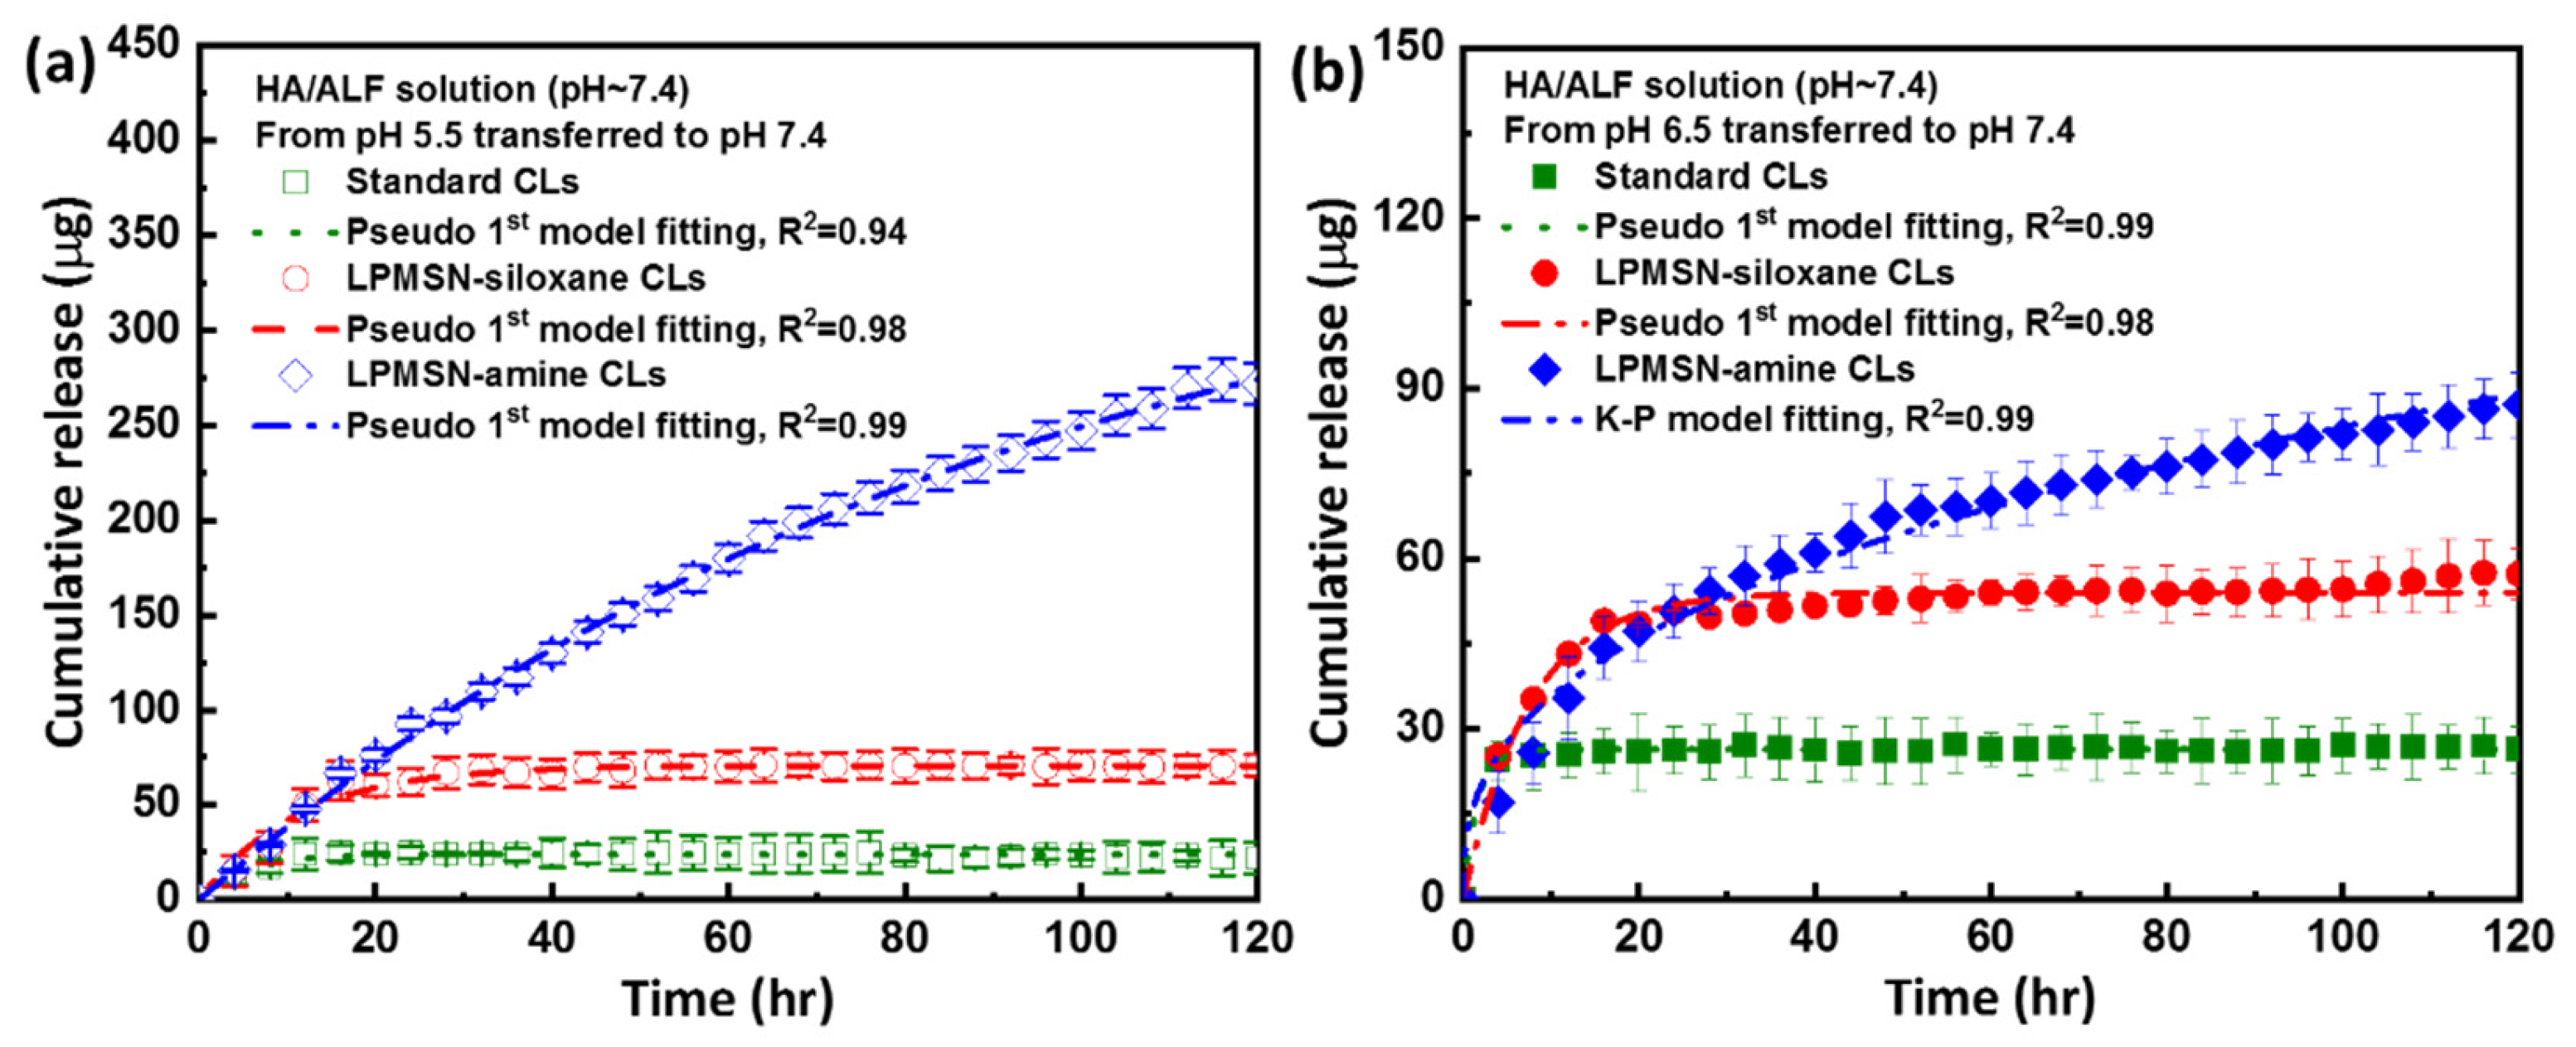

3.3. HA Loaded and Released of LPMSN-Laden CLs

3.4. HA Released Kinetics Mechanism of LPMSN-Laden CLs